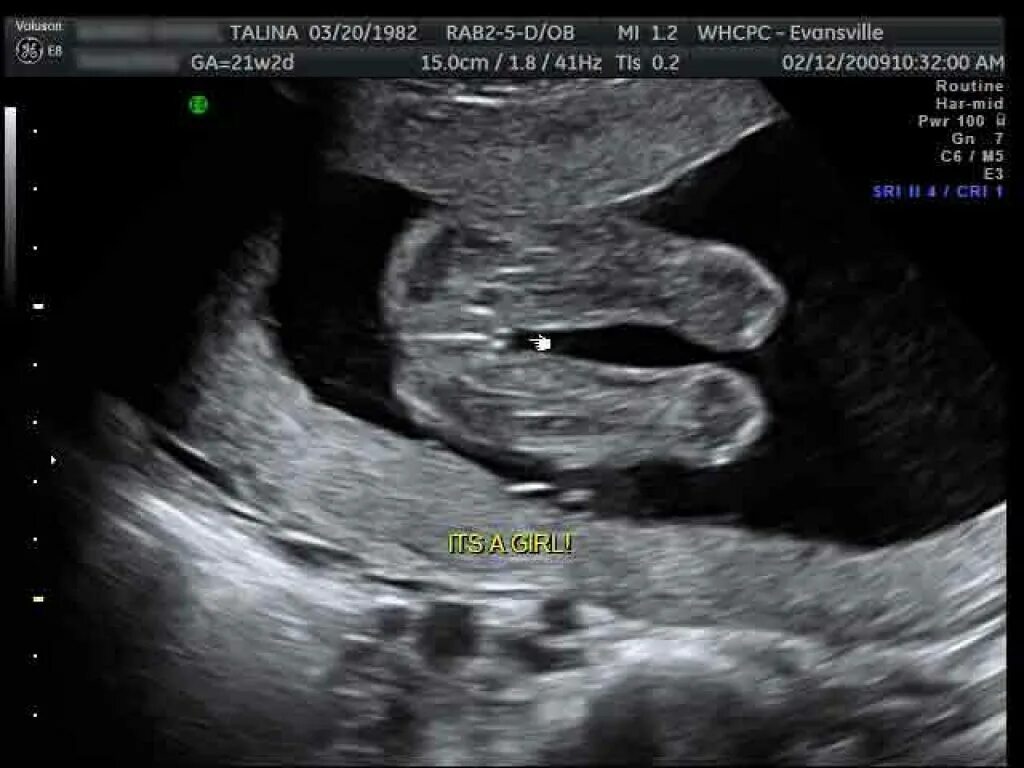

Узи 17 недель девочка